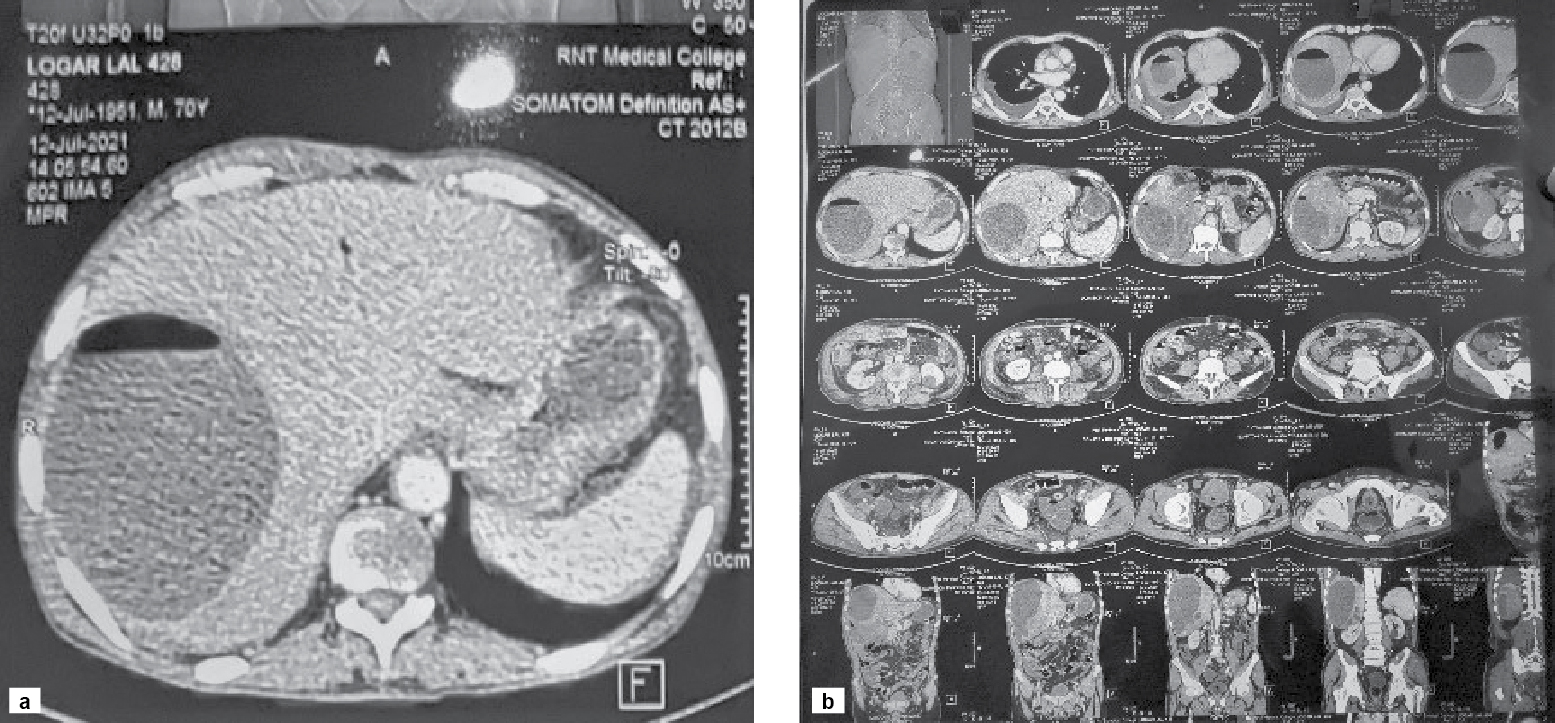

Abdominal ultrasound was done to look for possible cause of gas under right hemidiaphragm. Ultrasound abdomen showed moderate hepatomegaly with altered echotexture and abscess in right lobe of liver. After that, contrast-enhanced computed tomography (CECT) abdomen was performed which showed unruptured liver abscess as evident by intact capsule in right lobe and moderate hepatomegaly (Fig. 3 a and b).

Figure 3 a and b. CECT abdomen shows a large well defined peripherally enhancing hypodense lesion with air fluid level in segment VII of right lobe of liver extending into segment VI also.

A clear air fluid level was visible on CT film inside the liver abscess. Liver abscess was drained (approximately 2 lt.) after confirmation of diagnosis. Pus was light yellow with greenish hue and was sent for culture and sensitivity which showed the growth of K. pneumoniae, sensitive to piperacillin and tazobactam. Treatment with antibiotic therapy was started.

In this case, liver abscess filled with pus and having air fluid level visible in CECT abdomen, was responsible for gas under right dome of diaphragm in chest X-ray and X-ray FPA in erect posture.